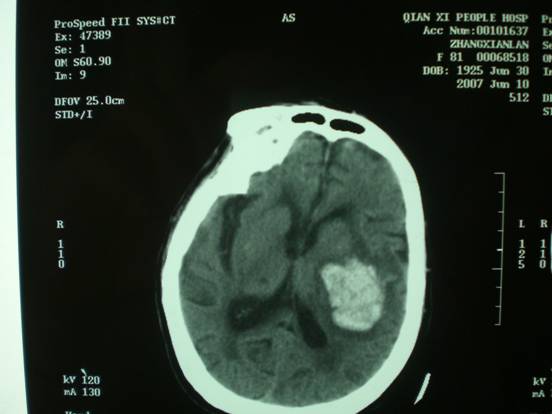

神内内科重点学科项目——锥颅血肿抽吸引流术治疗高血压性脑出血

重点学科项目名称:锥颅血肿抽吸引流术治疗高血压性脑出血

项目简介:此技术是我院神内二科于2007年初开展,至今已经额后部入路微创颅内血肿穿刺抽吸引流术治疗高血压性脑出血500余例。

项目优势:本手术方法具有创伤小、并发症发生率低、费用低廉且使患者缩短住院时间等优点,目前被广大患者所接受。近年我院神内二科广泛开展了高血压脑出血的微创穿刺治疗术,特别是改良后的穿刺术有如下优点: ①手术操作不受患者年龄和重要脏器功能限制,尤其高龄患者家属易于接受。只需局麻,操作迅速,大多30min内完成操作,即可清除部分血肿、降低颅内压,术后经血肿液化技术分次清除血肿,23d大部分患者能做到血肿大部清除。不易损伤血管和脑组织,不会因抽吸及引流过多造成颅内局部及全脑负压而再次出血。易固定,密闭性好,针孔只有3mm,无脑脊液漏;不易造成颅内感染。费用较常规开颅手术低,减轻患者负担。由于上述优点手术成功率达100%,近年完成病例数达500余例,总结工作成果,由我院独自承担完成额部入路微创穿刺术治疗高血压性基底核脑出血方法研究科研项目一项,2010年获河北省卫生厅科技进步二等奖。

适应人群:该项目适用于年老、体弱、合并多脏器疾病不宜开颅手术治疗的重症患者。

近年此操作技术被逐步规范和完善,应用范围逐渐扩大,目前已行多靶点穿刺+灌洗技术治疗重症脑出血继发脑室出血患者多例,均取得良好的临床效果。

(术前)

(术后)